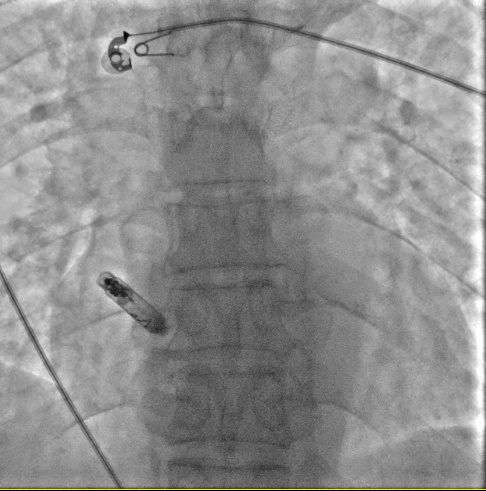

植入无导线起搏器的患者是一位60岁的男性,1个月前无明显诱因出现头晕不适,呈持续性,时重时轻,伴头闷、沉感,伴心悸,门诊以“头晕待诊”收住我院,临床诊断为心律失常,病态窦房结综合征。廉玉蓉团队经过与患者及家属的充分沟通,最终决定植入心房无导线起搏器。12月19日,廉玉蓉副主任医师团队通过患者股静脉路径,由输送导管将心房无导线起搏器精准输送至右心耳,牢固地锚定在右心耳基底部上。整个手术用时40分钟,顺利结束,术后程控显示阈值:0.5V/0.4ms、感知1.4mv、阻抗400Ω,起搏比例46%,预估使用寿命近10年。